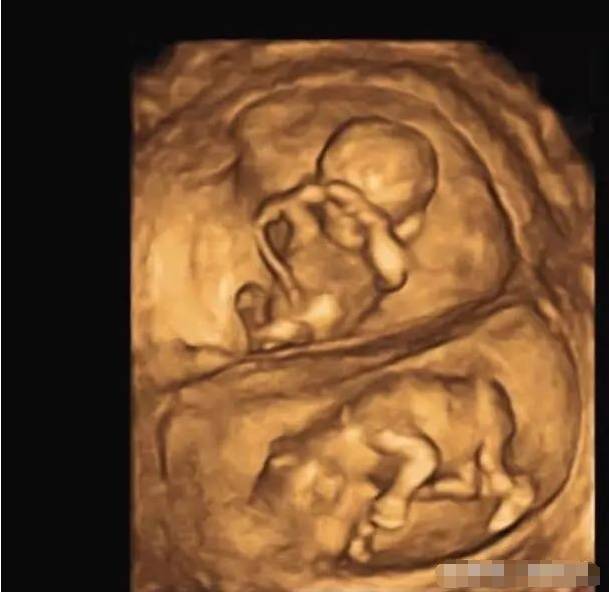

到底为什幺怀孕未满3个月不能说?许多人都以为是迷信,但妇产科医师苏怡宁说出了她的想法:“是有一定的道理在的!”

妇产科医师苏怡宁发文:“为什么习俗都告诉我们怀孕三个月以前都不要说呢?关于这件事情我必须说,这种说法确实还是有一定的道理在的,无关迷信,而是一种对于人生不确定性的敬畏。” 苏怡宁说:“统计上大约有三分之一到5分之一的胚胎,在12周之前,也就是三个月前会自然淘汰掉”“所以在真实的世界中,如果你太早告诉人家怀孕了,如果你真的不幸遇到在三个月之前流产了,接下来的日子遇到朋友不间断的关心,那可能是一次又一次的锥心之痛,当然至于谁该说谁不该说,就得自己拿捏喔。”

“在情感上,三个月内尽量低调不要公布,或者,尽量不要揭露人家早期怀孕的讯息,多给些体谅、多留些空间、少给些压力。多给些体谅,多留些空间,少给些压力,我想,这会是很贴心的事。”网友看完也纷纷留言:“没错,我就是怕这样,结果我上一个公公讲的全家族都知道,没多久小孩有问题,我整个伤心又尴尬很久”“我曾经怀孕九周流产...胚胎忽然没了心跳!只能引产!在诊间哭的乱七八糟⋯”“同感,满三个月后也是有风险,更何况是未满三个月的不确定性太多。”